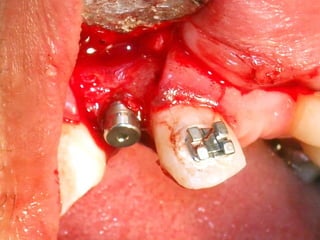

Plastia de maxilares para implantes dentales.

La conformación quirúrgica de un contorno alveolar adecuado es

determinante para la correcta aplicación y aceptación de los implantes

de titanio, aquí proponemos una técinica para lograr el espesor óseo

suficiente y la corrección estética del proceso, ya que antiguamente al

extraer un diente se acostumbraba presionar las tablas alveolares

“para cohibir la hemorragia”, con el colapso subsiguiente de la región.

La aplicación de implantes requiere de una cantidad y calidad de hueso

Importantes para sostener el metal en un área de estroma óseo

Saludable. Esto se logra efectuando una valoración adecuada de las

Características sistémicas del paciente y no injertando hueso o haciendo

Plastías indiscriminadamente.